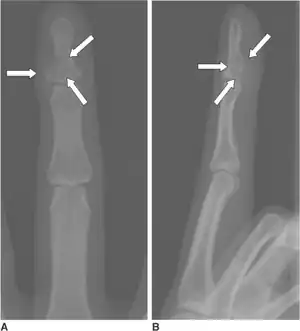

| Calcifying aponeurotic fibroma-a,b)Show eccentrically located osteolytic lesion at base of distal phalanx | |